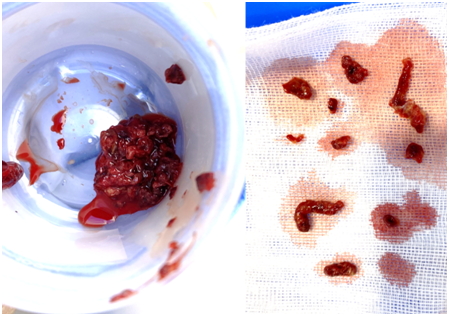

前因后果清楚了,那如何处理呢?很快,在厦心超声科的辅助下,庄晖对小胡进行了手术,先是找到了她小腿残留很短的一段健康静脉,然后通过超声引导精确穿刺,建立了手术的入路。在抽出大量血栓之后,小胡的腿部静脉终于恢复了通畅,而髂静脉狭窄也在造影下显露出来。在髂静脉狭窄的位置植入支架,扩开了静脉,让左腿的血液顺畅地回到了肺部和心脏。术后第二天,小胡就可以下地行走,两条腿都恢复了正常。

附图1:从小胡腿上抽取出的血栓